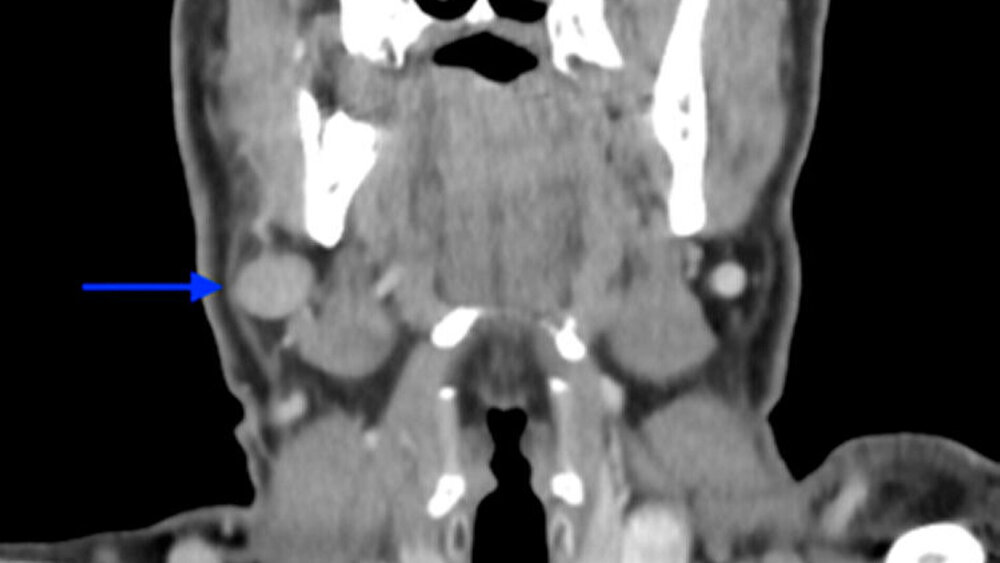

Anhand der klinischen Beurteilung wurde die Verdachtsdiagnose eines Plattenepithelkarzinoms gestellt. Differenzialdiagnostisch kam eine Epulis in Betracht. Zur Beurteilung der Befundausdehnung sowie zur Planung der weiteren Therapie wurde ein CT des Halses mit Kontrastmittel im Rahmen des Stagings durchgeführt. Im CT konnte das Ausmaß der Osteolysen ermittelt werden. Zu dem Zeitpunkt hatte keine Arrosion der Kortikalis stattgefunden (Abbildung 3). Darüber hinaus zeigten sich zahlreiche prominente und insbesondere rechtsseitig vergrößerte zervikale Lymphknoten, welche als metastasenverdächtig eingestuft wurden (Abbildung 4). Aufgrund der unklaren Dignität des Befundes erfolgte zur histologischen Diagnosesicherung die ambulante Probeentnahme in regio 048.